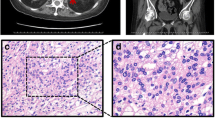

Complete blood count, urine analysis, and renal and liver function tests were all normal. A biochemical evaluation revealed elevated 24-hour urinary free cortisol (UFC) 306.8 μg/24 hours (reference range 3.5 to 45 μg/24 hours), elevated cortisol level, and suppressed ACTH level with loss of their normal diurnal rhythm. Her cortisol level was 634 ug/L at 8 a.m., 621 ug/L at 4 p.m., and 521 ug/L at 0 a.m. (reference range 62 to 194 ug/L), while her ACTH level was always < 1 ng/L (reference range 7.2 to 63.6 ng/L). Serum cortisol remained unsuppressed after 1 mg overnight and high-dose dexamethasone suppression tests (at 624 ug/L and 607 ug/L, respectively). Serum thyroid function tests were normal; anti-thyrotropin receptor antibody (TRAb), anti-thyroid peroxidase (TPOAb), and anti-thyroglobulin antibodies (TGAb) were negative. Plasma potassium was 2.2~3.0 mmol/L. Glycated hemoglobin (HbA1c) was 8.7%. Serum androgen, aldosterone/renin activity ratio, and 24-hour urinary catecholamines were all in the normal range. Glucagon, luteinizing hormone-releasing hormone (LHRH), mixed meal, postural, metoclopramide, and vasopressin tests were performed in order to evaluate aberrant hormonal responses. Results were positive for vasopressin and upright posture test. Computed tomography (CT) imaging of her adrenal glands revealed bilateral multiple lobular masses (Fig. 1a, b); magnetic resonance imaging (MRI) of her orbits indicated bilateral exophthalmos with hypertrophy of the retro-orbital fat (Fig. 1c); MRI of her pituitary was normal (Fig. 1d). Diagnosis of PBMAH was made and our patient underwent bilateral laparoscopic adrenalectomy. Gross pathological examination of adrenal glands showed each gland contained several nodules (Fig. 1e). Pathological findings were consistent with PBMAH: multinodular glands with homogenous, golden-yellow-colored nodules. Nodules contained predominantly fascicular cells (Fig. 1f). After surgery, her plasma cortisol and ACTH at 8 a.m. were 6.06 ug/L and 1.87 ng/L respectively, indicating a successful surgery. Hydrocortisone supplementation was given as well, as she was started on metformin for diabetes. At 6-month follow-up, her blood glucose levels were well controlled and her blood pressure was 120/80 mmHg without use of any antihypertensive medication. The exophthalmos improved markedly after the surgery.

Clinical features of the patient with primary bilateral macronodular adrenal hyperplasia. Computed tomography scan of adrenal glands showed massive enlargement of the adrenal glands and multiple nodules (as shown by arrows) (a, b). Magnetic resonance imaging of the orbital showed bilateral exophthalmos (c). MRI of the pituitary gland was normal (d).Gross pathology of the resected left adrenal gland with nodules of various sizes (e). Histological view of resected adrenal tissue showing the presence of large cortical cells shown by hematoxylin and eosin stain at magnification × 100 (f)